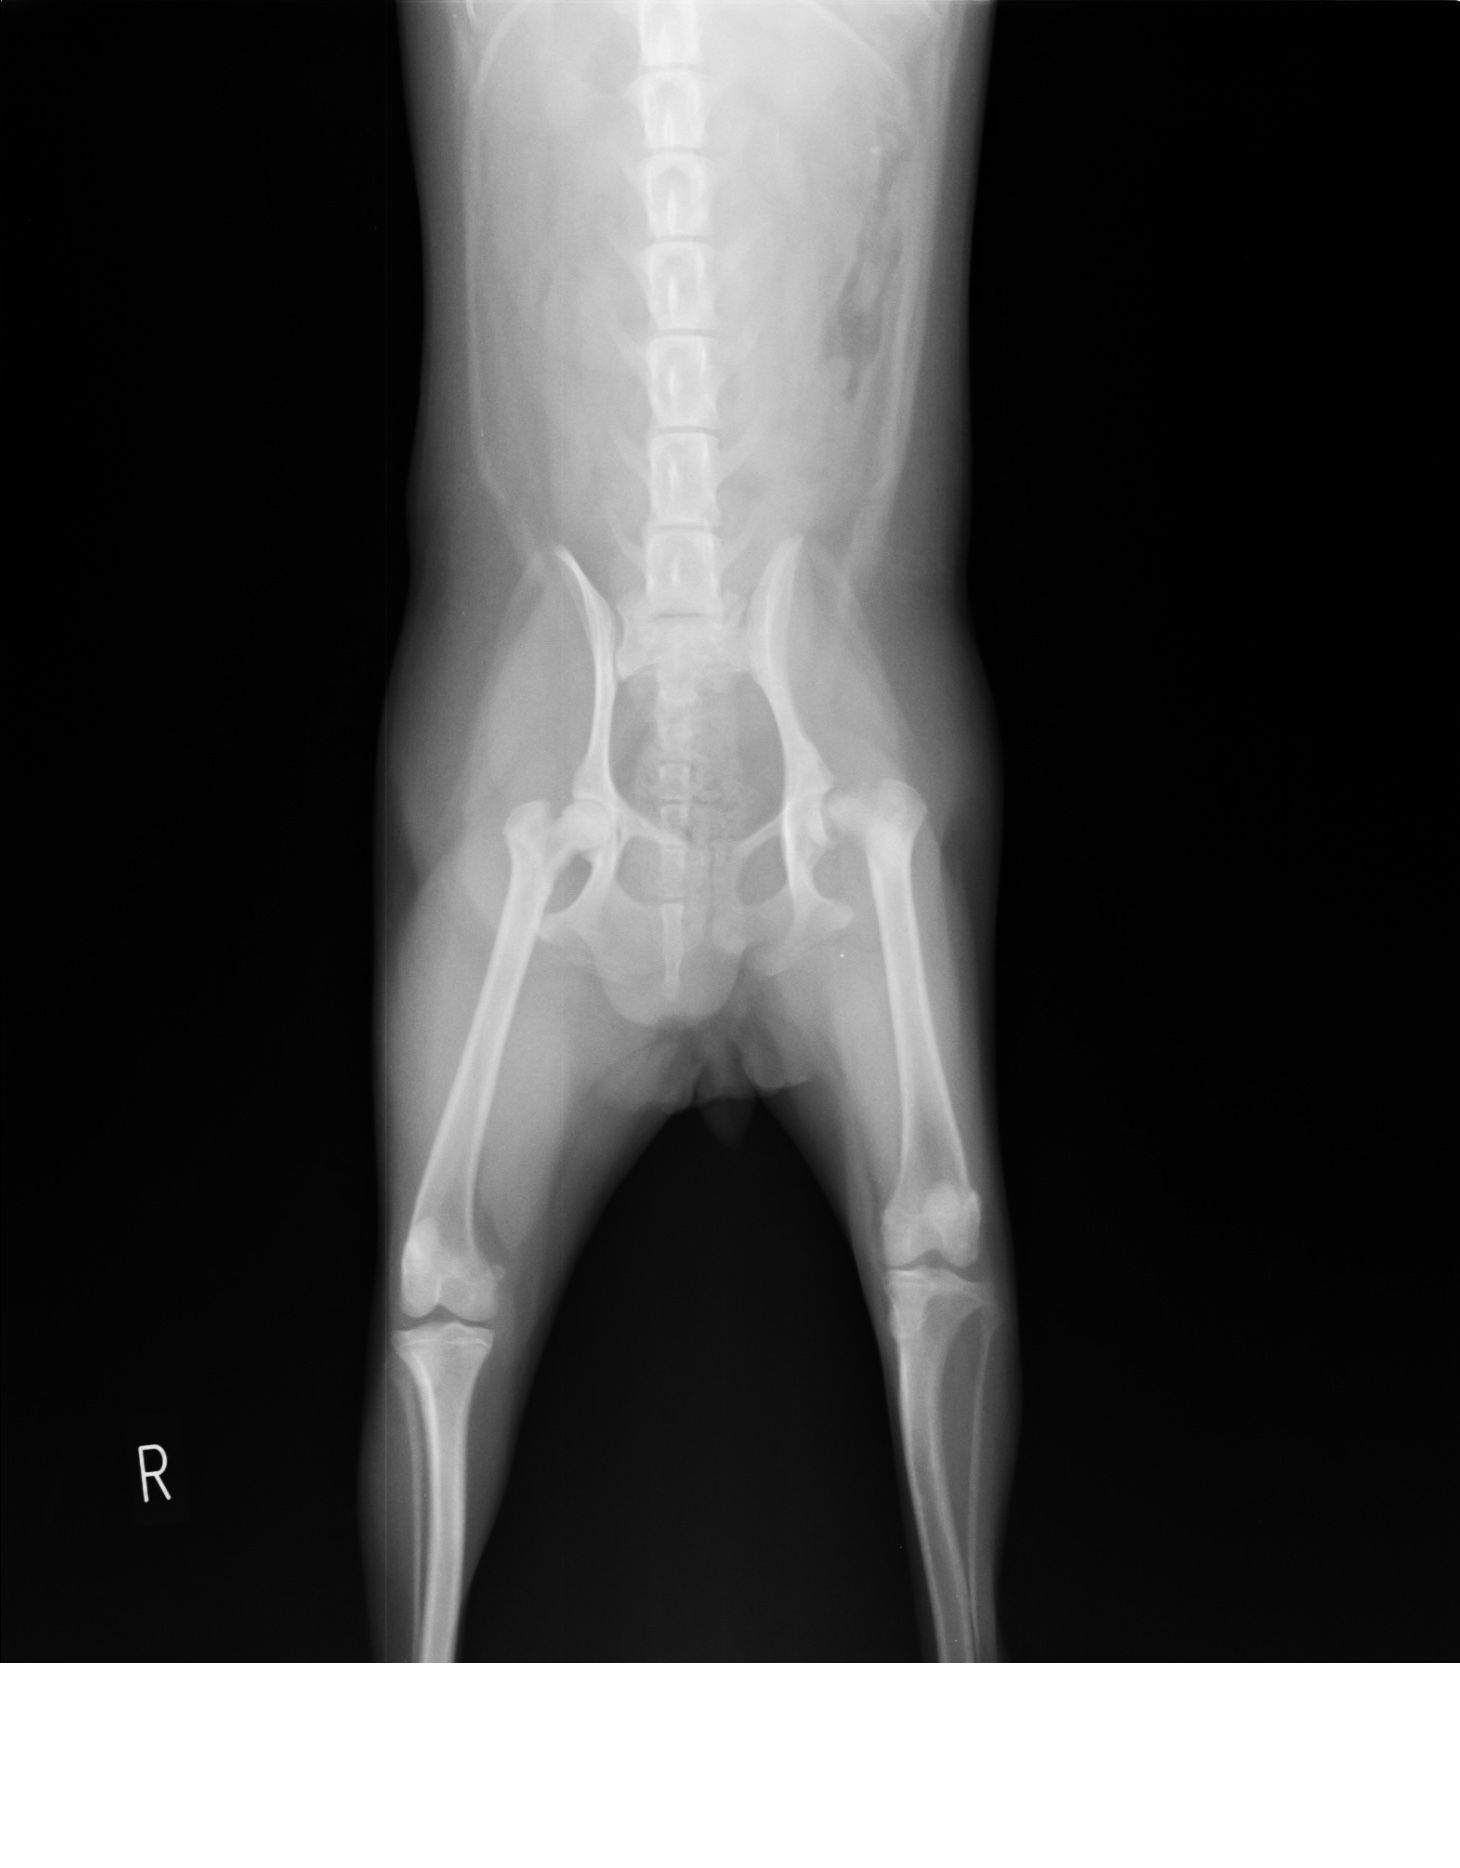

レッグ・カルべ・ペルテス病(無菌性大腿骨頭壊死症)

トイ・プードル

10ヶ月齢

避妊済み雌

約1ヶ月続く左後ろ足の跛行を主訴に、他院さんから紹介受診されました。レントゲン検査、臨床症状、若齢であることなどから無菌性大腿骨頭壊死症と診断し、大腿骨頭骨頸部切除術を行いました。現在リハビリ中ですが、順調に回復中です。

無菌性大腿骨頭壊死症は、大腿骨頭の骨端板が閉鎖していない若齢期に、大腿骨頭の非炎症性壊死を呈する疾患です。明らかな原因は解明されていませんが、成長期に大腿骨頭へ血液供給をする外側骨端動脈が閉塞することで、大腿骨頭の虚血性壊死が生じることが示唆されています。平均発症年齢が7.7ヶ月と報告されており、発生が早いのが特徴です。お薬での治癒は期待できないため、基本的には外科手術が必要になります。

左大腿骨頭は骨折していました

骨盤と大腿骨が離れているように見えますが、しばらくすると偽関節が形成されて正常と変わらず歩行できるようになります